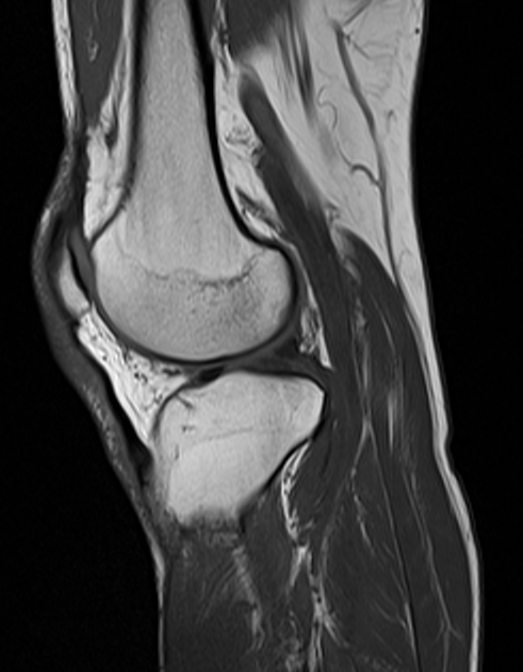

- 자기 공명 영상 (Magnetic Resonance Imaging, MRI): 강력한 자기장과 전파를 이용하여 인체의 단면 영상을 얻는 기법이다. 연조직의 대조도가 뛰어나 뇌, 척추, 근골격계 질환 진단에 유용하다.

MRI는 강력한 자기장을 사용하여 신체 조직 내의 원자핵(보통 수소 양성자)을 정렬한 다음, 전파 신호를 사용하여 이러한 핵의 회전축을 교란시키고 핵이 기준 상태로 돌아올 때 생성되는 전파 신호를 관찰한다.[10] 전파 신호는 코일이라고 하는 작은 안테나에 의해 수집되며, 관심 영역 근처에 배치된다. MRI의 장점은 축 방향, 관상 방향, 시상 방향 및 여러 사선 방향으로 영상을 쉽게 생성할 수 있다는 것이다. MRI 스캔은 모든 영상 촬영 기법 중에서 가장 우수한 연조직 대비를 제공한다. 스캔 속도와 공간 해상도의 발전, 컴퓨터 3D 알고리즘 및 하드웨어의 개선으로 MRI는 근골격 방사선학 및 신경 방사선학에서 중요한 도구가 되었다.

단점 중 하나는 영상 촬영 동안 환자가 시끄럽고 좁은 공간에서 오랫동안 가만히 있어야 한다는 것이다. MRI 검사를 중단할 정도로 심각한 폐쇄공포증(밀폐된 공간에 대한 공포)은 환자의 최대 5%에서 보고된다. 더 강력한 자기장(3 테슬라), 검사 시간 단축, 더 넓고 짧은 자석 구멍 및 더 개방된 자석 설계를 포함한 자석 설계의 최근 개선으로 폐쇄공포증 환자에게 어느 정도 안도감을 주었다. 그러나 동등한 자기장 강도의 자석의 경우 영상 품질과 개방형 설계 사이에는 종종 절충이 있다. MRI는 뇌, 척추 및 근골격계를 영상화하는 데 큰 이점이 있다. MRI 사용은 현재 심장 박동기, 인공 와우, 일부 체내 투약 펌프, 특정 유형의 뇌 동맥류 클립, 눈 속의 금속 조각, 강력한 자기장으로 인한 일부 금속 하드웨어, 신체가 노출되는 강력한 변동 전파 신호가 있는 환자에게는 금기시된다. 잠재적 발전 분야에는 기능적 영상, 심혈관 MRI 및 MRI 유도 치료가 포함된다.